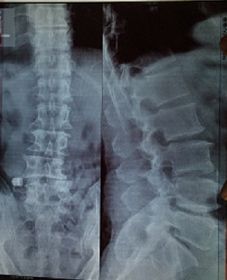

二零一七年四月二十六日,这个邻居腿腰痛的受不了了,就去医院,结果医生拍的片子是脊骨下五段不直了,骨头增生,右大腿钻轴不圆了。邢台治不了,得去北京军医院手术。

'邻居脊骨下五段片'

邻居脊骨下五段片